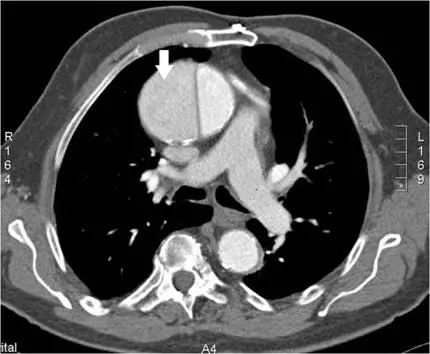

下圖箭號所指最可能的解剖部位為何?

本圖為靜脈顯影劑注射後的胸部增強 CT(contrast-enhanced chest CT),為橫斷面軸位影像(axial view),掃描層面位於心臟及大血管層級,右側標記為 R、左側標記為 L(影像右下角見「A4」層面標示)。

圖中可見以下主要結構(由前至後、由右至左):

- 前方正中偏右(白色箭號所指):一個大型、圓形、對比劑均勻強化的血管結構,其位置位於心臟前縱隔正中偏右的位置,管腔大、增強顯著 — 此為升主動脈。

- 升主動脈左後方:略橢圓形、較升主動脈偏左的大血管 — 此為主肺動脈(main pulmonary artery)。

- 升主動脈右側:較細的圓形血管結構 — 此為上腔靜脈(SVC)。

- 後方正中偏左:圓形血管,為降主動脈(descending aorta)。

白色箭號明確指向位於前縱隔中央偏右的最大、最亮增強之圓形血管,即升主動脈